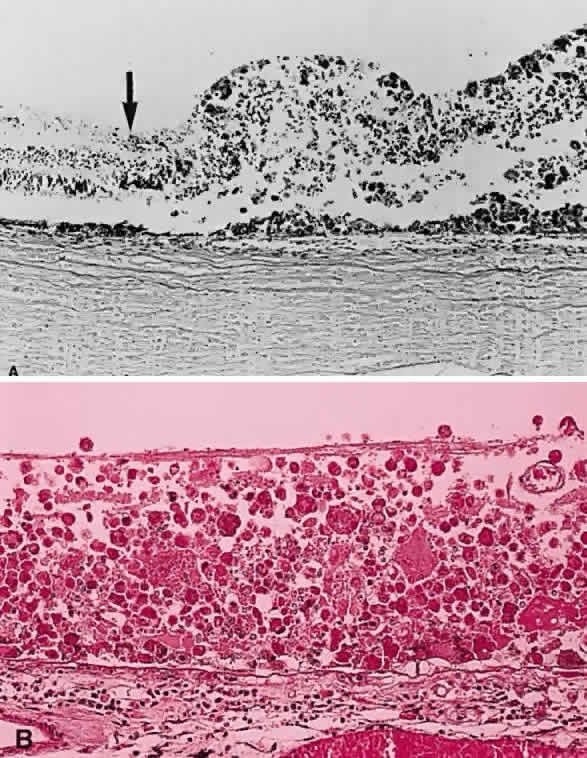

Fig. 17. A. A histologic section stained with H & E demonstrating vascularized

membranes on the disc and retina. Tractional retinal detachment is present. Notice

the subretinal fluid (amorphous eosinophilic material). B. Fundus photograph of fibrous tissue emanating from the disc in patient

with proliferative diabetic retinopathy. The disc is pale; the macula

is edematous with exudate. Pigmented laser spots are visible temporally. Fig. 17. A. A histologic section stained with H & E demonstrating vascularized

membranes on the disc and retina. Tractional retinal detachment is present. Notice

the subretinal fluid (amorphous eosinophilic material). B. Fundus photograph of fibrous tissue emanating from the disc in patient

with proliferative diabetic retinopathy. The disc is pale; the macula

is edematous with exudate. Pigmented laser spots are visible temporally.